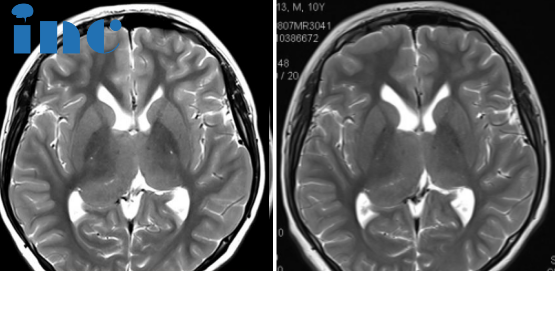

病史摘要:2022年4月1日,涛涛因头部受伤进行头颅CT检查,结果是头部有钙化灶。7月15日,父母带涛涛到医院查头颅MRI平扫+增强,诊断结果是双侧丘脑胶质瘤可能。7月26日,再次到医院查头颅MR波谱成像(MRS),诊断结果是右侧丘脑恶性肿瘤。随后又到北京某医院问诊说可以手术,但是无法全切,且手术风险很大。涛涛目前还没有明显的症状,只是偶尔在走路的时候会突然绊一下。如果手术后,孩子变得比现在状态更差,涛涛父母犹豫了。手术还是不手术,他们多方打听之下,决定咨询国际颅底脑干手术教授巴特朗菲教授,想要听听他的意见。

INC巴教授远程评估意见:

对比2022年和的影像,我监测不到肿瘤有任何生长,很明显这是一个钙化的低级别胶质瘤。CT扫描很好地显示了右侧肿瘤内的强化的钙化。

在这种情况下,特别是考虑到这个男孩的临床状况良好,我们可以通过反复的核磁共振成像检查对他的病例进行跟踪,因此,如果出现任何变化,我们都可以很容易地发现。

不过,这种肿瘤很有可能在多年内保持稳定,而且,在接下来的几年里,当男孩继续生长时,肿瘤甚至可能出现退化(肿瘤体积可以在不治疗的情况下缩小)。当然,这只是一种可能性,我们当然不能确定这种有利的发展过程是否真的会发生,但至少有很大的机会出现这种有利的情况。

至于体重增加,也许是因为下丘脑也受累了,因为下丘脑与丘脑紧密相连,也许也含有小部分肿瘤。因此,男孩需接受儿科肿瘤专家的诊治,检查全部(下丘脑相关的)激素,并根据具体情况替代激素。不过,要阻止下丘脑肿瘤引起的体重增加并不容易,因为目前还没有合适的药物。